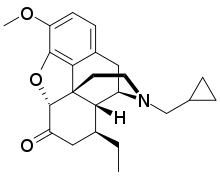

Oripavine derivatives

Thienorphine

- 7-PET

- Acetorphine

- Alletorphine (N-allyl-noretorphine)

- BU-48

- Buprenorphine

- Buprenorphine-3-glucuronide

- Cyprenorphine

- Dihydroetorphine

- Etorphine

- Homprenorphine

- 18,19-Dehydrobuprenorphine (HS-599)

- N-cyclopropylmethylnoretorphine

- Nepenthone

- Norbuprenorphine

- Norbuprenorphine-3-glucuronide

- Thevinone

- Thienorphine

Structures

| Oripavine derivatives | ||||

|---|---|---|---|---|

7-PET 7-PET |

Acetorphine Acetorphine |

Alletorphine Alletorphine |

BU-48 BU-48 |

Buprenorphine Buprenorphine |

Cyprenorphine Cyprenorphine |

Dihydroetorphine Dihydroetorphine |

Etorphine Etorphine |

Homprenorphine Homprenorphine |

18,19-Dehydrobuprenorphine 18,19-Dehydrobuprenorphine |

N-cyclopropylmethylnoretorphine N-cyclopropylmethylnoretorphine |

Nepenthone Nepenthone |

Norbuprenorphine Norbuprenorphine |

Thevinone Thevinone |

Thienorphine Thienorphine |